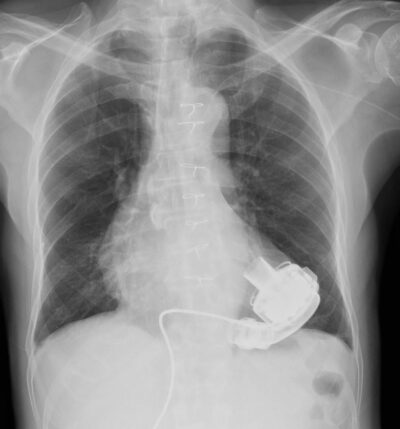

A left ventricular assist device, or lvad, is a mechanical pump that is implanted inside a person's chest to help a weakened heart pump blood

Unlike a total artificial heart, the. Do you know how to triage and treat lvad patients? A left ventricular assist device (lvad) is a mechanical pump that providers implant in people who have heart failure The device helps the lower left chamber (left ventricle) of your heart pump blood out of the ventricle to your aorta and the rest of your body.

A left ventricular assist device (lvad) is placed in the chest It helps pump blood from the lower left heart chamber, called the left ventricle, to the rest of the body. Lvad failure is the most important etiology of cardiac arrest that the ed physician should know how to manage There are 3 reasons for possible lvad failure